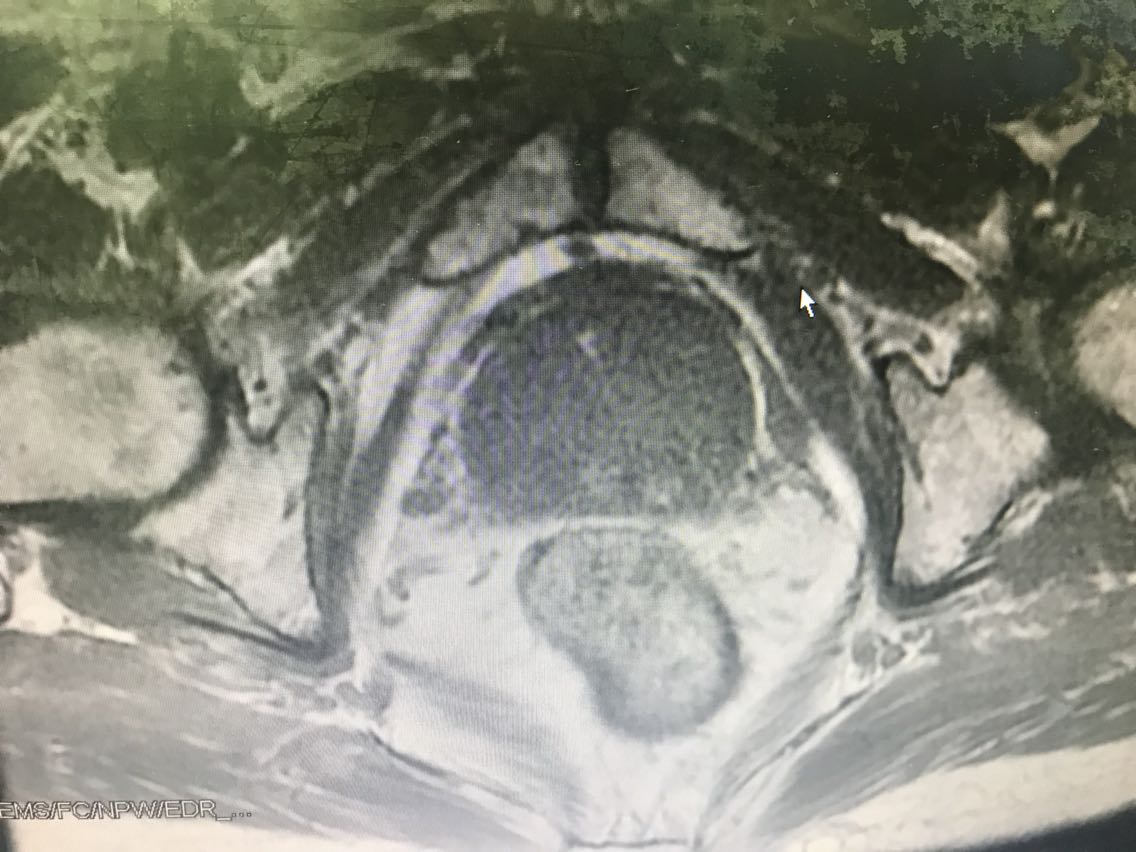

患者男性,77岁。 主诉:血尿7+月 现病史:入院前7+月,患者出现血尿,于外院体检查示PSA升高(10.62),服药血尿控制(具体药物不详),无尿频、尿急、下腹疼痛等不适,为求进一步诊治于我院门诊就诊,查前列腺MRI:前列腺尖部右侧中央带结节及9-10点结节,多系前列腺癌。门诊行前列腺穿刺活检示:编号1、2、3、4、5、6查见前列腺腺癌,Gleason评分4+3=7分。门诊以“前列腺癌”收入我科。患病来精神、睡眠、食欲可,大小便无异常,体重无明显变化。 既往史无特殊。

查体:腹部平软,无压痛及反跳痛,双肾及输尿管走行区无压痛,肾区无叩痛。直肠指检:前列腺Ⅱ°大,双侧质硬,右侧叶扪及约1cm硬结。 辅助检查: 前列腺MRI(2018-6-14,本院):前列腺尖部右侧中央带结节及9-10点结节,多系前列腺癌,累及右侧外周带 前列腺穿刺活检示(2018-6-28,本院):编号1、2、3、4、5、6查见前列腺腺癌,Gleason评分4+3=7分。